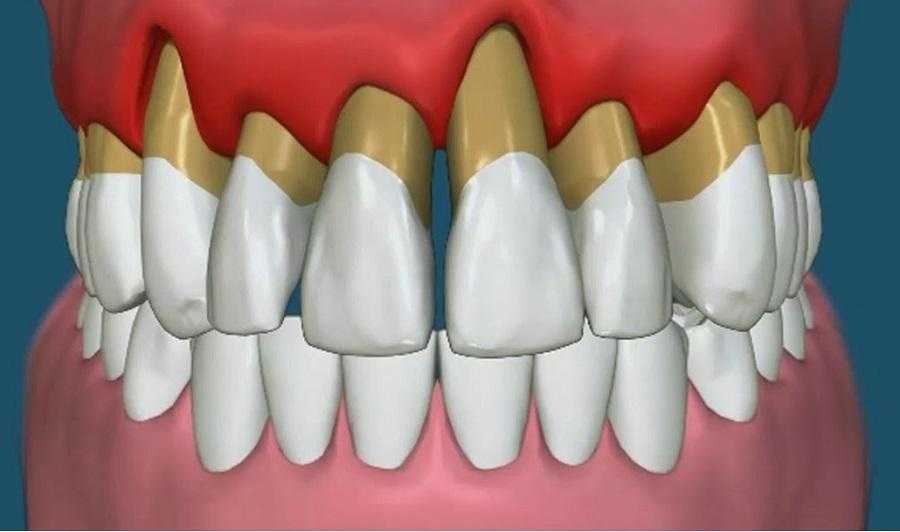

Развивается пародонтит.

Это заболевание, при котором происходят дистрофические изменения в костях челюсти и деснах. Развивается оно постепенно, незаметно, но приводит к расшатыванию зубов. Линия десны приподнимается, обнажая шейку зуба – переходную часть между коронкой и корнями.

Пародонтит